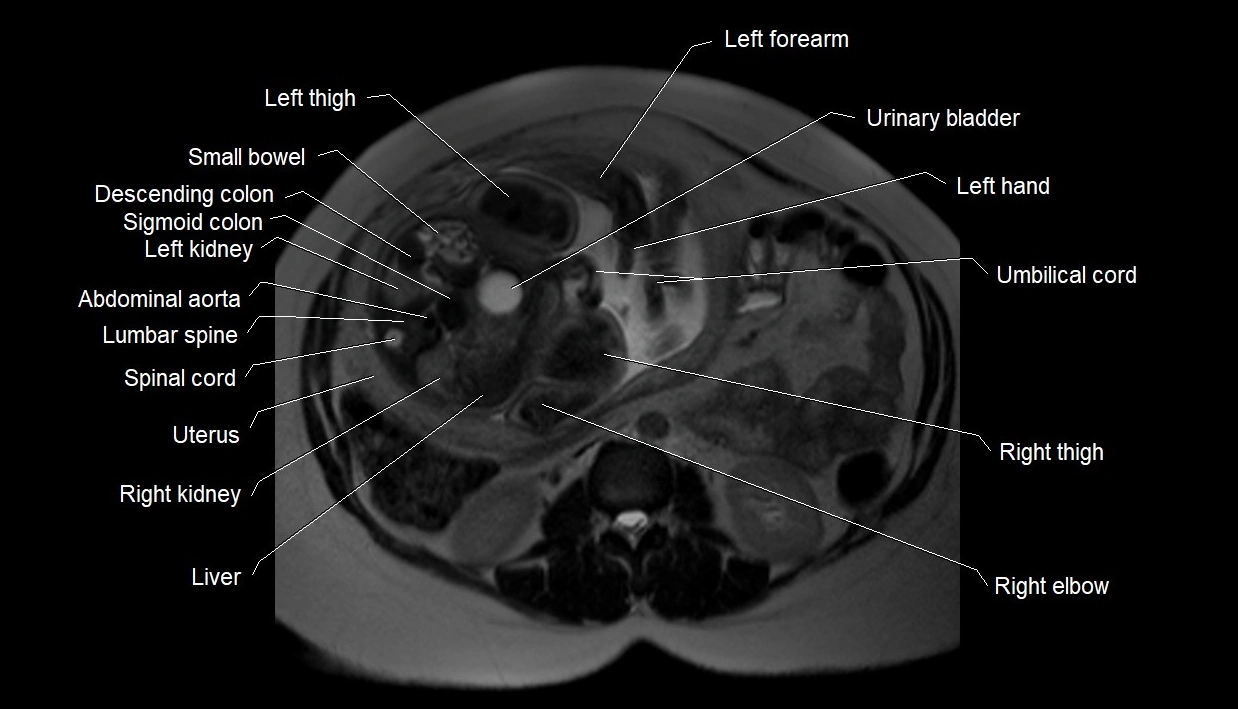

MRI Appearance

T2 HASTE (T2 GRE):

• Amniotic fluid shows very bright hyperintense signal

• Provides natural contrast against fetus and placenta

• Small particles (vernix) may appear as scattered hypointense foci within bright fluid

T1 GRE:

• Amniotic fluid shows low signal intensity (dark)

• Hemorrhage, infection, or proteinaceous content may cause focal or diffuse high signal intensity

MRI image

image